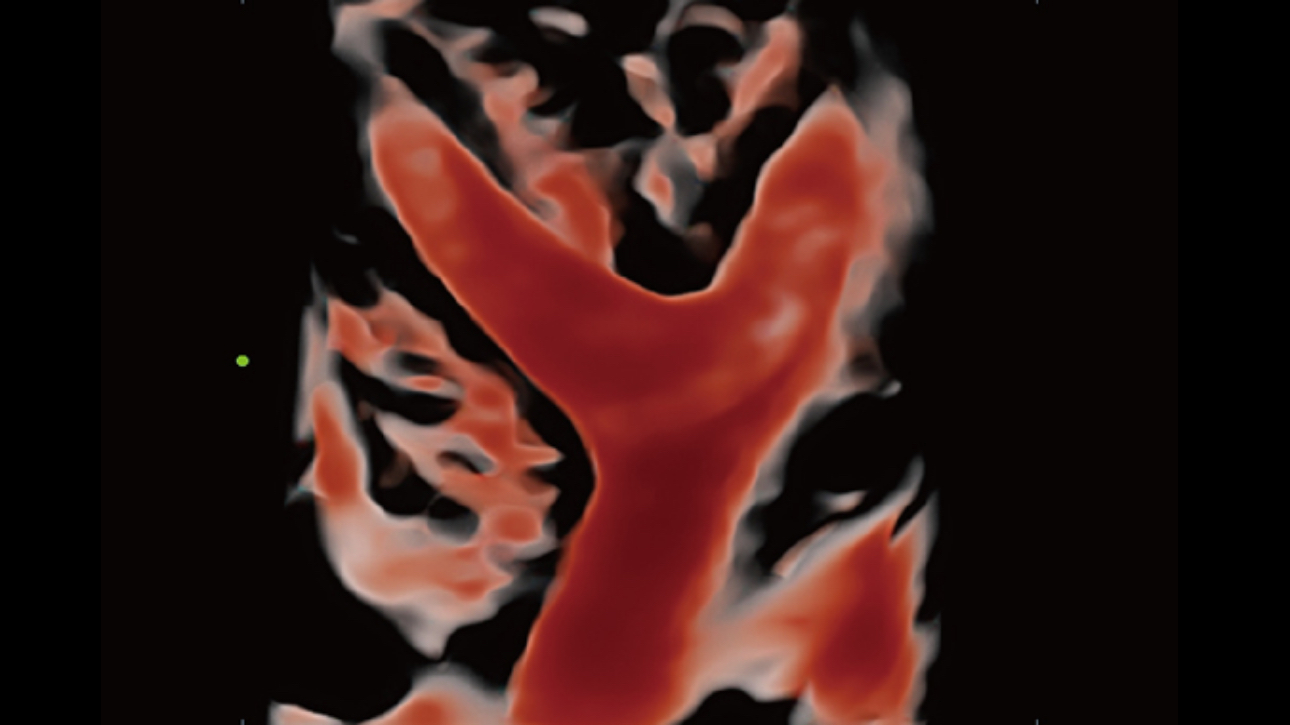

The channel data based ZST+ is an extraordinary innovation, representing an ultrasound evolution. Transforming ultrasound metrics from conventional beamforming to channel data based processing; ZST+ is able to deliver multiple imaging advances: Advanced Acoustic Acquisition, Dynamic Pixel Focusing, Sound Speed Compensation, Enhanced Channel Data Processing and Total Recall Imaging.

As ZST+ captures and stores the complete acoustic raw data set. Total Recall Imaging allows system to do retrospective processing on channel data and also permits users to modify numerous imaging parameters on stored images to maximize clinical output.

Powered by the channel data based ZST+ platform, the new Resona 6 with Zone Intelligence builds up a truly smart mechanism to deliver a new level of intelligence.The core of Zone Intelligence is deep learning that is based on big data base and Ultrasound expertise

As a result, it is able to provide multiple intelligent retrospective processing, leading to efficient and effective image visualization, plane recognition, measurement, and image enhancement .